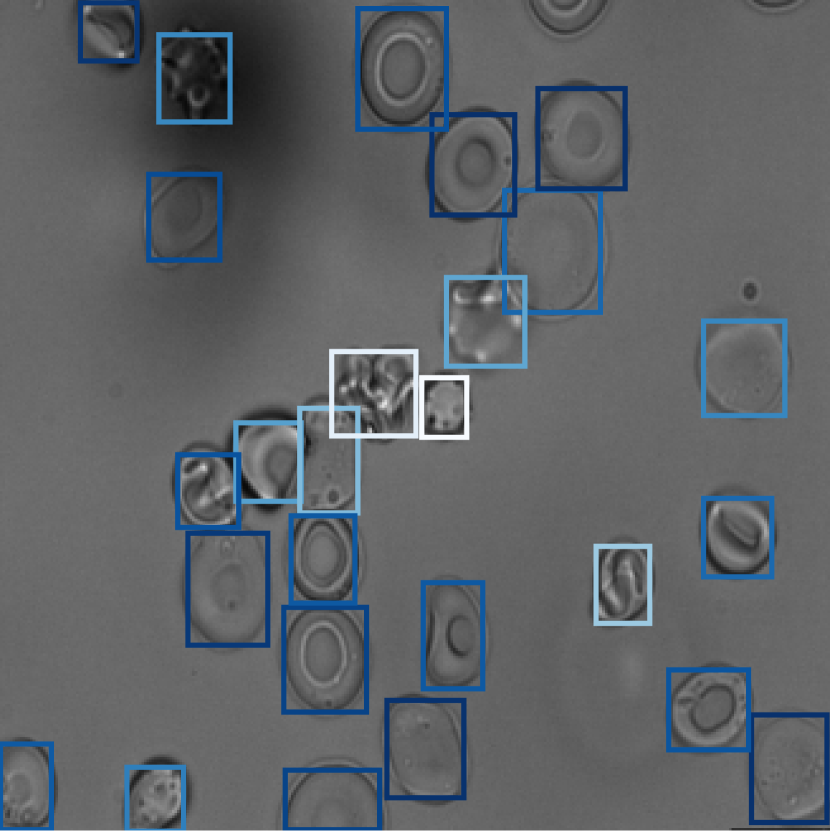

3.3 Anomaly recognition

When our model estimates the distribution of control cells, high anomaly scores should be able to identify anomalous cells, whether the training set contains them or not. This property of our method is useful for detecting anomalies in rare or unseen classes during training. To examine our method in this context, we trained the model with the two HHA classes SCD and Thalassemia, separately. Then, we tested the model with unseen class samples and measured their anomaly and attention scores. Fig. 5 shows the results, where the small distribution of anomalous cells is clearly indicating anomaly awareness of the model. For both experiments, the distribution of scores in the control class is also shown.

Refer to caption

Figure 5: Distribution of anomaly scores compared to attention scores for SCD and Thal classes when their samples were absent during the training. Our method still can assign high anomaly scores to abnormal cells.